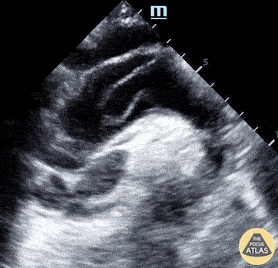

Thoracic Aortic Dissection & Aneurysm - Suprasternal View of Type A Dissection

Suprasternal notch view shows a mobile intimal dissection flap in the aortic arch. Michael Cover, MD @michaelc0ver